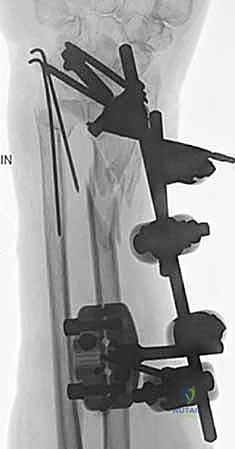

ثانياً: العلاج الجراحي (Surgical Intervention)

متى يقرر الدكتور هطيف ضرورة التدخل الجراحي؟

1. عدم الاستقرار (Instability): إذا كان المفصل الزندي الكعبري البعيد (DRUJ) غير مستقر بعد تثبيت كسر الكعبرة.

2. الانزياح (Displacement): إذا كان الكسر في قاعدة الناتئ الإبري منزاحًا بأكثر من 2 ملم.

3. الكسور المفصلية: أي كسر يخل بتطابق السطح المفصلي لرأس الزند.

4. الكسور المفتتة: في الجزء الكردوسي التي تؤدي إلى قصر عظم الزند.

5. الكسور المفتوحة (Open Fractures): حيث يبرز العظم من الجلد، وتتطلب جراحة طارئة لتنظيف الجرح وتثبيت الكسر لمنع العدوى.

التخطيط الجراحي لكسور الزند

تُعد جراحات المعصم والزند من الجراحات الدقيقة التي تتطلب مهارة عالية، وهو المجال الذي يتفوق فيه الأستاذ الدكتور محمد هطيف بفضل استخدامه لتقنيات الجراحة المجهرية (Microsurgery) والأدوات الجراحية ذات التقنية العالية.

1. التخطيط ما قبل الجراحة (Pre-operative Planning)

يقوم الدكتور هطيف بدراسة الأشعة المقطعية ثلاثية الأبعاد بدقة، ويختار نوع وحجم الصفائح المعدنية (Plates) والمسامير (Screws) المناسبة لكل مريض بناءً على حجم العظم ونوع الكسر.